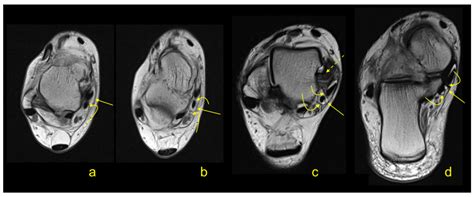

To diagnose issues related to the flexor retinaculum, medical professionals typically perform a physical examination. The Tinel’s sign test—tapping over the area of the retinaculum to elicit tingling in the foot—is a standard diagnostic indicator. Imaging studies such as Ultrasound or MRI are frequently used to visualize the thickness of the retinaculum and identify any cysts, scar tissue, or anatomical variations that may be contributing to nerve compression.